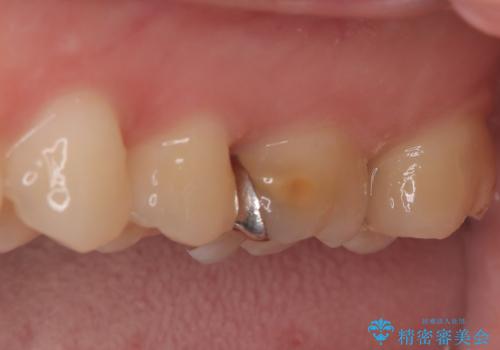

経過観察と土台作り: 一定期間の経過を観察し、痛みや炎症がないことを確認。神経の生存を確認した上で、セラミックを支えるための土台を精密に構築しました。

セラミックによる修復: 最終的な被せ物(または詰め物)にはセラミックを使用しました。高い適合性により、二次的な虫歯のリスクを抑えつつ、天然歯のような自然な咬み心地と美しさを再現しました。